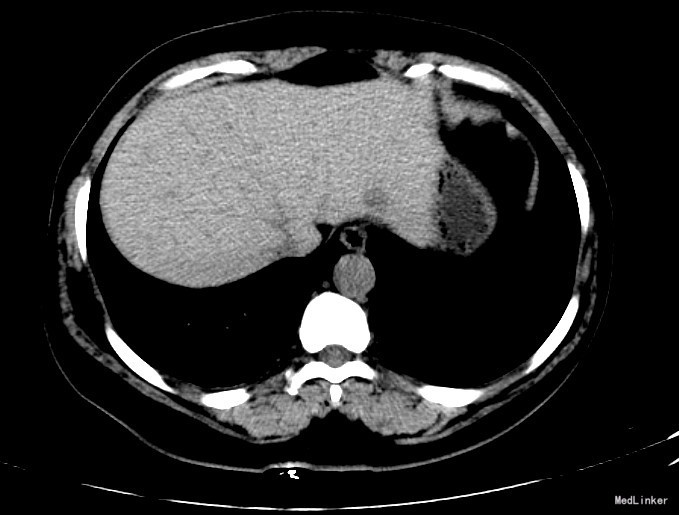

查体:体格检查:体温36.4℃,脉搏72次/分,呼吸18次/分,血压120/70毫米汞柱,神志清,状态可,皮肤及巩膜无黄染,手掌赤痕阳性,红丝赤缕阴性,心肺听诊未闻异常,腹软,无压痛,肝脾肋下未及,移动性浊音阴性,双下肢无浮肿,扑翼样震颤阴性,舌象:舌淡红、苔薄白,脉象:弦脉。 化验:血细胞分析:白细胞计数 6.3 10^9/L、红细胞计数 4.73 10^12/L、血小板计数 175.0 10^9/L、血红蛋白 156 g/L,肝功酶谱:丙氨酸氨基转移酶 22 U/L、碱性磷酸酶 84 U/L、白蛋白 43.8 g/L、总胆红素 13.3 umol/L,甲胎蛋白测定:甲胎蛋白 182.80 ng/mL 彩超:符合慢性肝损伤,肝右叶高回声性质待定0.7cm 肝弹性测定:CAP 252 E 6.9 增强CT:脾大,肝硬化?肝内多发RN,大小约1.2cm,Ⅱ段结节合并Ca变可能性大

诊断:1.乙肝肝硬化 活动性 代偿期 C-P分级 A级 5分 2.肝占位(不除外HCC) 治疗:患者乙肝肝硬化患者,多次于我院中医科住院治疗,本次住院期间中医理疗、抗病毒治疗,查甲胎蛋白增高,并且增强CT发现肝内可疑病灶,考虑原发性肝癌可能性大,于局麻下行TACE治疗,术中诊断为原发性肝癌以微导管超选S2段肝动脉一分支,造影明确为肿瘤供血动脉,注入混悬液(碘化油5毫升+雷替曲塞2毫克)3.2毫升,栓塞微球0.1毫升。